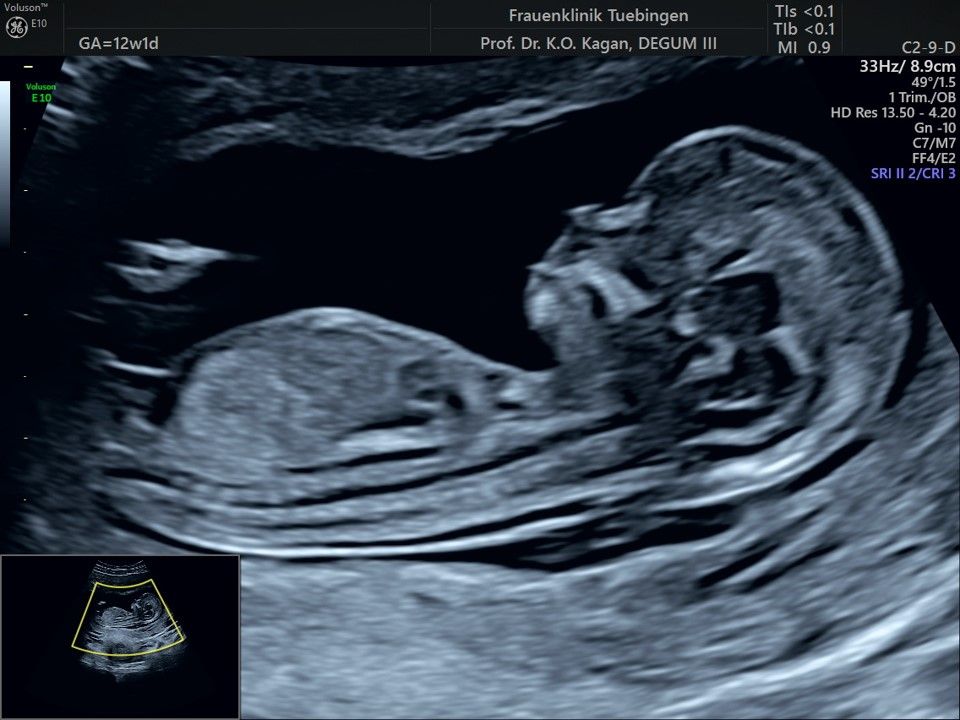

Im Rahmen des Ersttrimester-Screenings untersuchen wir die Organe des Feten mittels Ultraschall. Dabei machen wir auch gerne ein Bild für Sie.

Obwohl der Fet zu diesem Zeitpunkt erst zwischen 5 und 8cm groß ist, lassen sich bereits etwa die Hälfte aller schwerwiegenden Fehlbildungen erkennen bzw. ausschließen. Sollten wir eine Auffälligkeit sehen, werden wir mit Ihnen den Befund und das weitere Vorgehen ausführlich besprechen.

Die eigentliche Organuntersuchung findet um die 20.SSW (zweites Screening) statt. Das Ersttrimester-Screening und das zweite Screening sind sich ergänzende Untersuchungen und ersetzen sich gegenseitig nicht.

Das Ergebnis der Ultraschalluntersuchung ist wegweisend. Dabei wird der Fet vermessen, die Organe werden untersucht und die sonographischen Marker zur Risikoberechnung für Chromosomenstörungen werden beurteilt. Das sind: die Nackentransparenzdicke, Nasenbein sowie der Blutfluss in der rechten Herzhälfte und im Ductus venosus, einem Gefäß in der Leber des Feten.